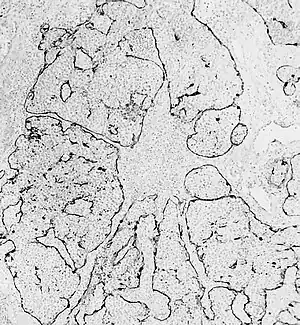

Esthesioneuroblastoma is of neurocrest origin, arising from olfactory sensory cells in the olfactory epithelium.[1] The olfactory epithelium consists of olfactory sensory cells, sustentacular cells and basal cells.[1] Esthesioneuroblastoma consists of lobular sheets with neurofibrullar fibers and rosettes.[4] Hyam's classifications are an important way of determining prognosis.[10]

Hyam's histopathological grades for esthesioneuroblastoma[11]

| Grade | Lobular architexture preservation | Mitotic index | Nuclear polymorphism | Fibrillary matrix | Rosettes | Necrosis |

|---|---|---|---|---|---|---|

| I | + | none | none | prominent | Homer Wright (HW) rosettes | none |

| II | + | low | moderate | present | HW rosettes | none |

| III | +/- | moderate | prominent | low | Flexner-Wintersteiner rosettes | rare |

| IV | +/- | high | marked | absent | none | frequent |